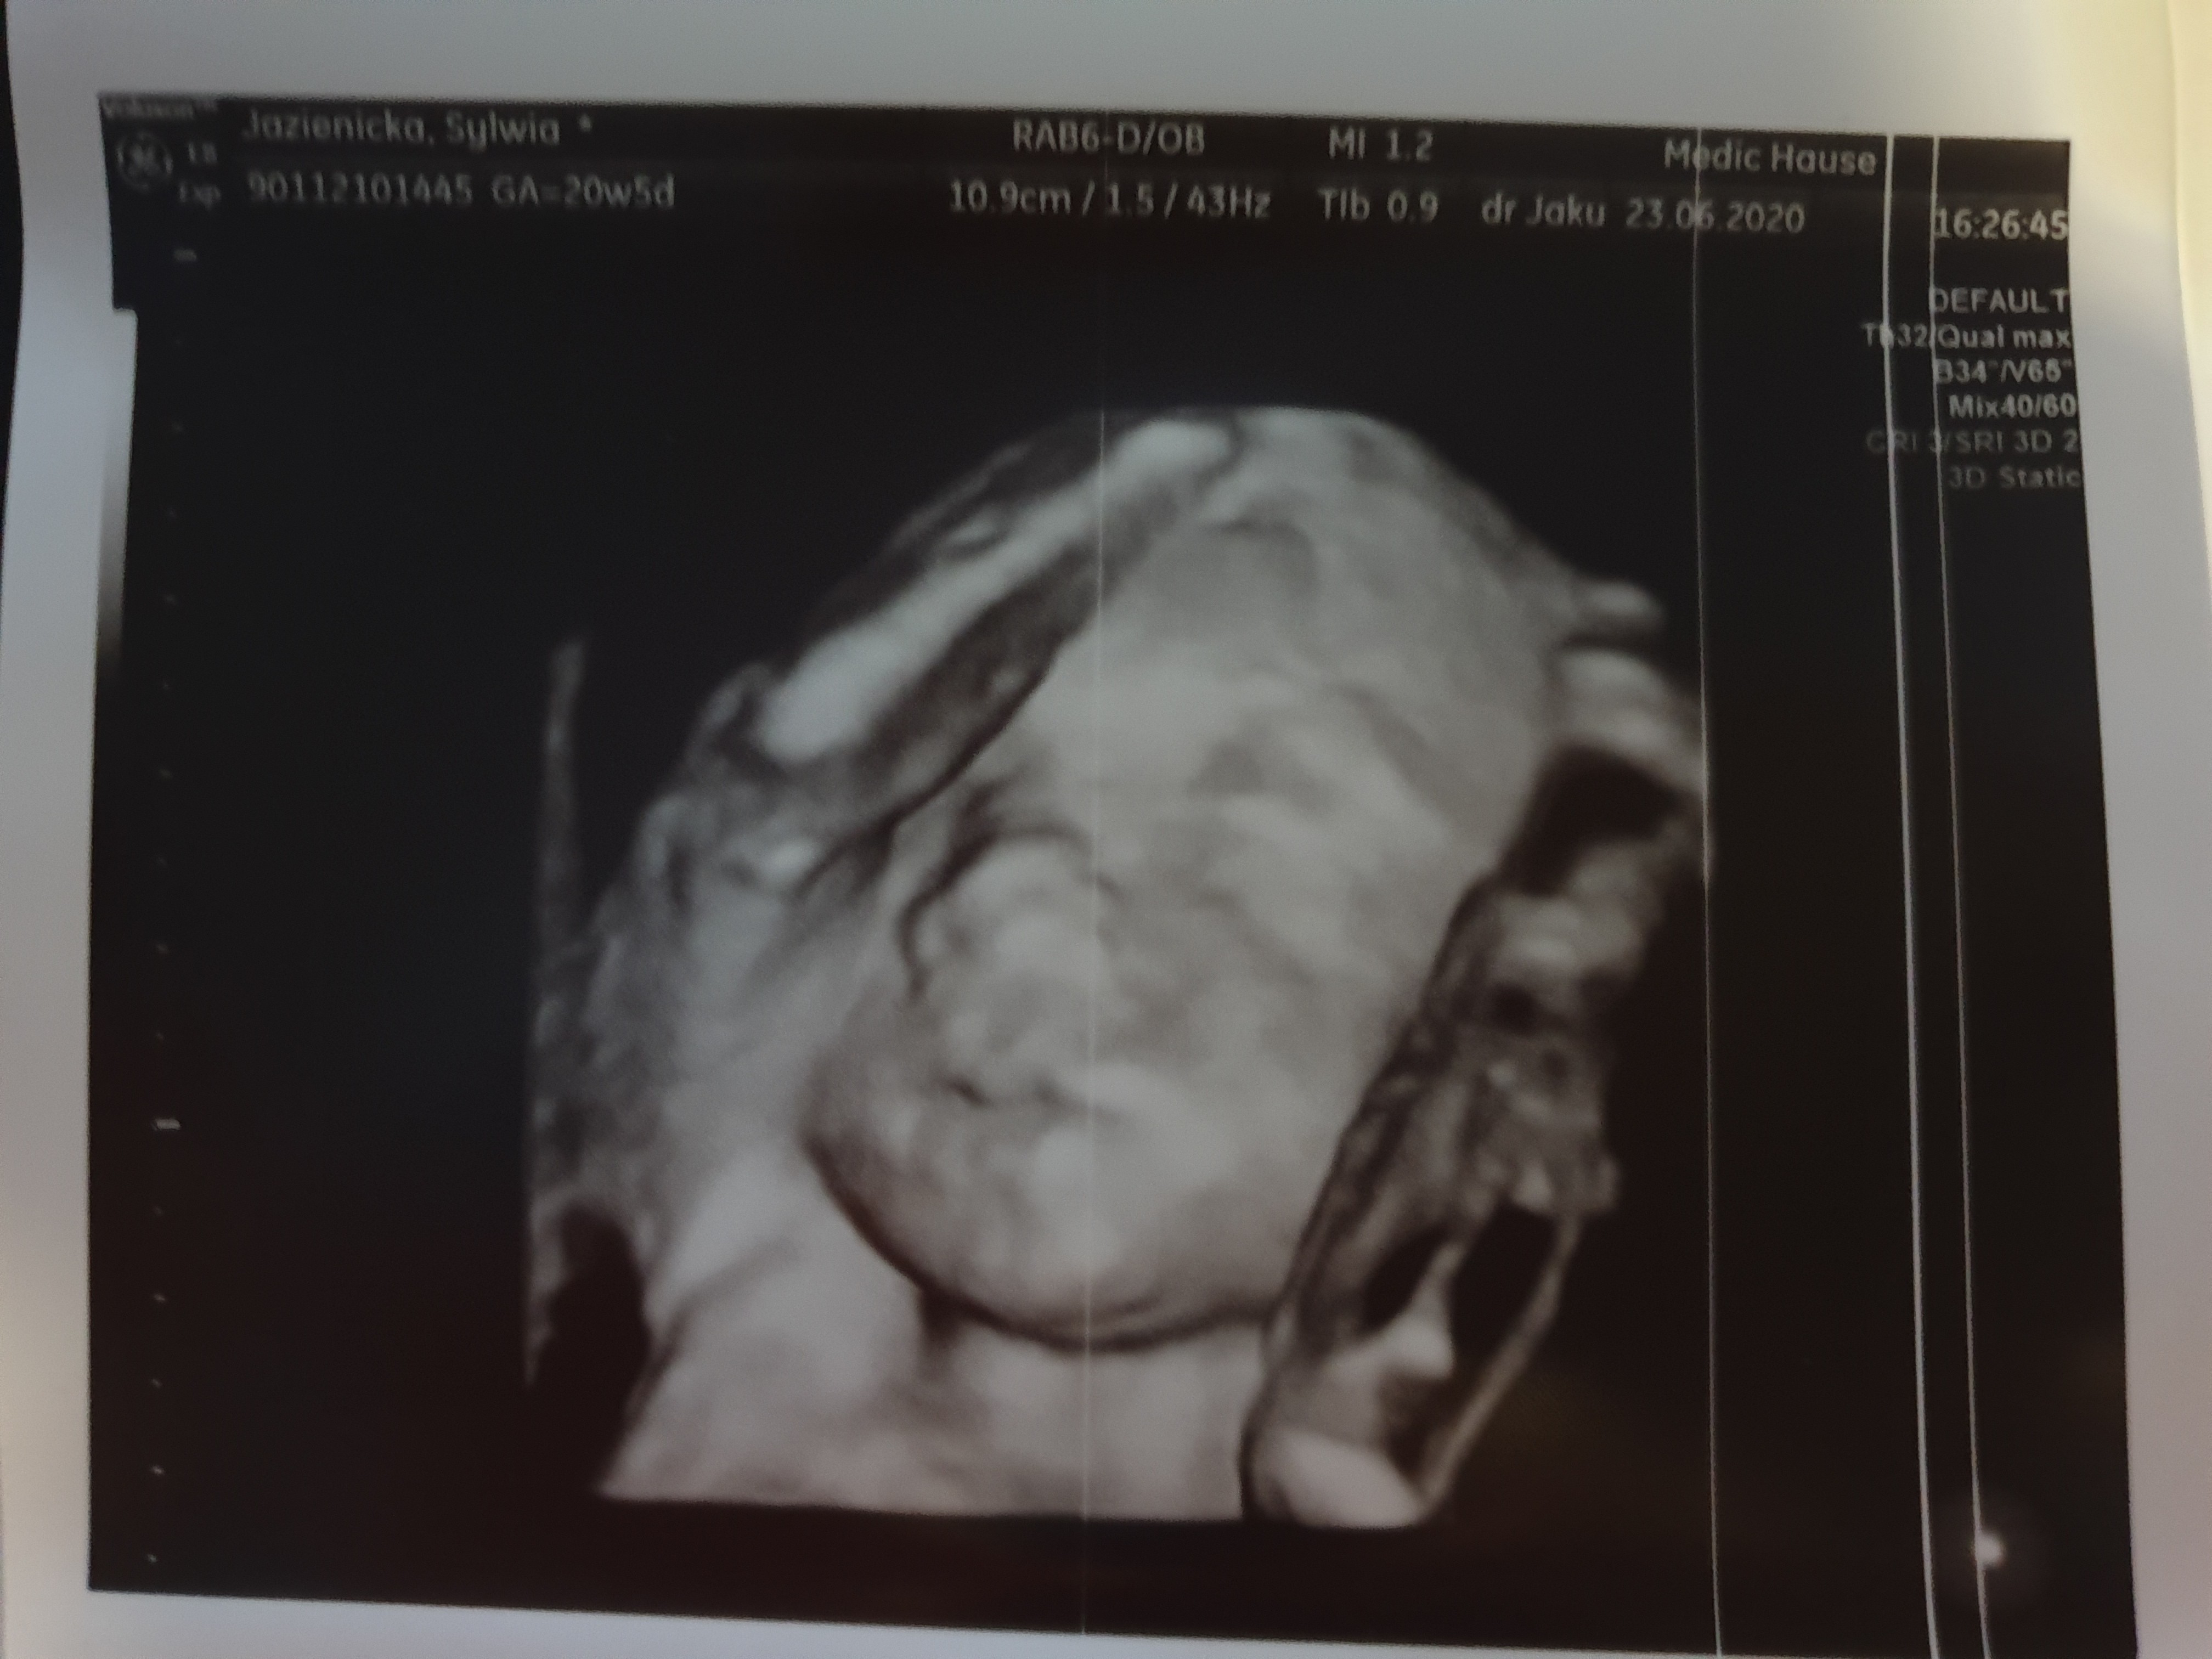

Rośnie uparte stworzenie, nie chciał się mały pokazać i skakałam w gabinecie przez 40 min, spacer i jeszcze raz USG ale udało się wszystko sprawdzić :)

Waży całe 420g więc jest dosyć duży, ale ja mam 178 cm wzrostu, sama urodzilam się jako klocek więc to nic dziwnego :)